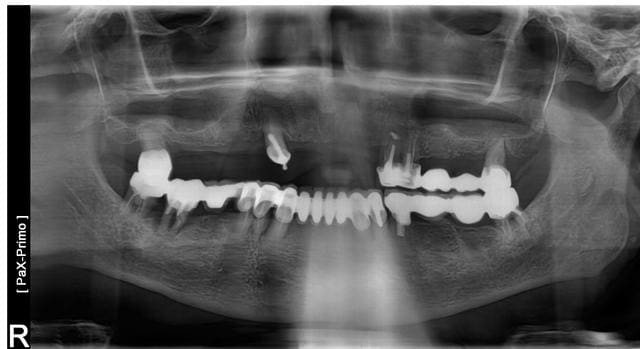

ce patient de 84 se presente car son stellite manque de retention. Pas de probleme de santé.

La racine de 14 est a extraire et la 18 aussi. Le patient ne veux pas toucher au brige 24 28, et ne possede pas un budget a rallonge pour envisager de tout remplacer par des implants.

J'envisage de poser trois implants en 12 22 et14 pour faire attachements boule ou une barre sur ces trois implants dans un premier temps et quand le bridge secteur 2 ne tiendra plus je pouurais poser un en 24 pour faire une barre sur 4 implants et prothese complete supra implantaire stabilisée par 4 implants.

Tu n'a pas le choix, mettre des implants avec un terrain paro comme celui ci, c'est franchement risqué.